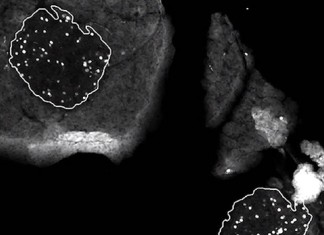

tPA: el protector del cerebro

Desde su introducción en la década de 1990, la droga "anticoagulante" tPA ha sido considerado como un "arma de doble filo" para las personas...